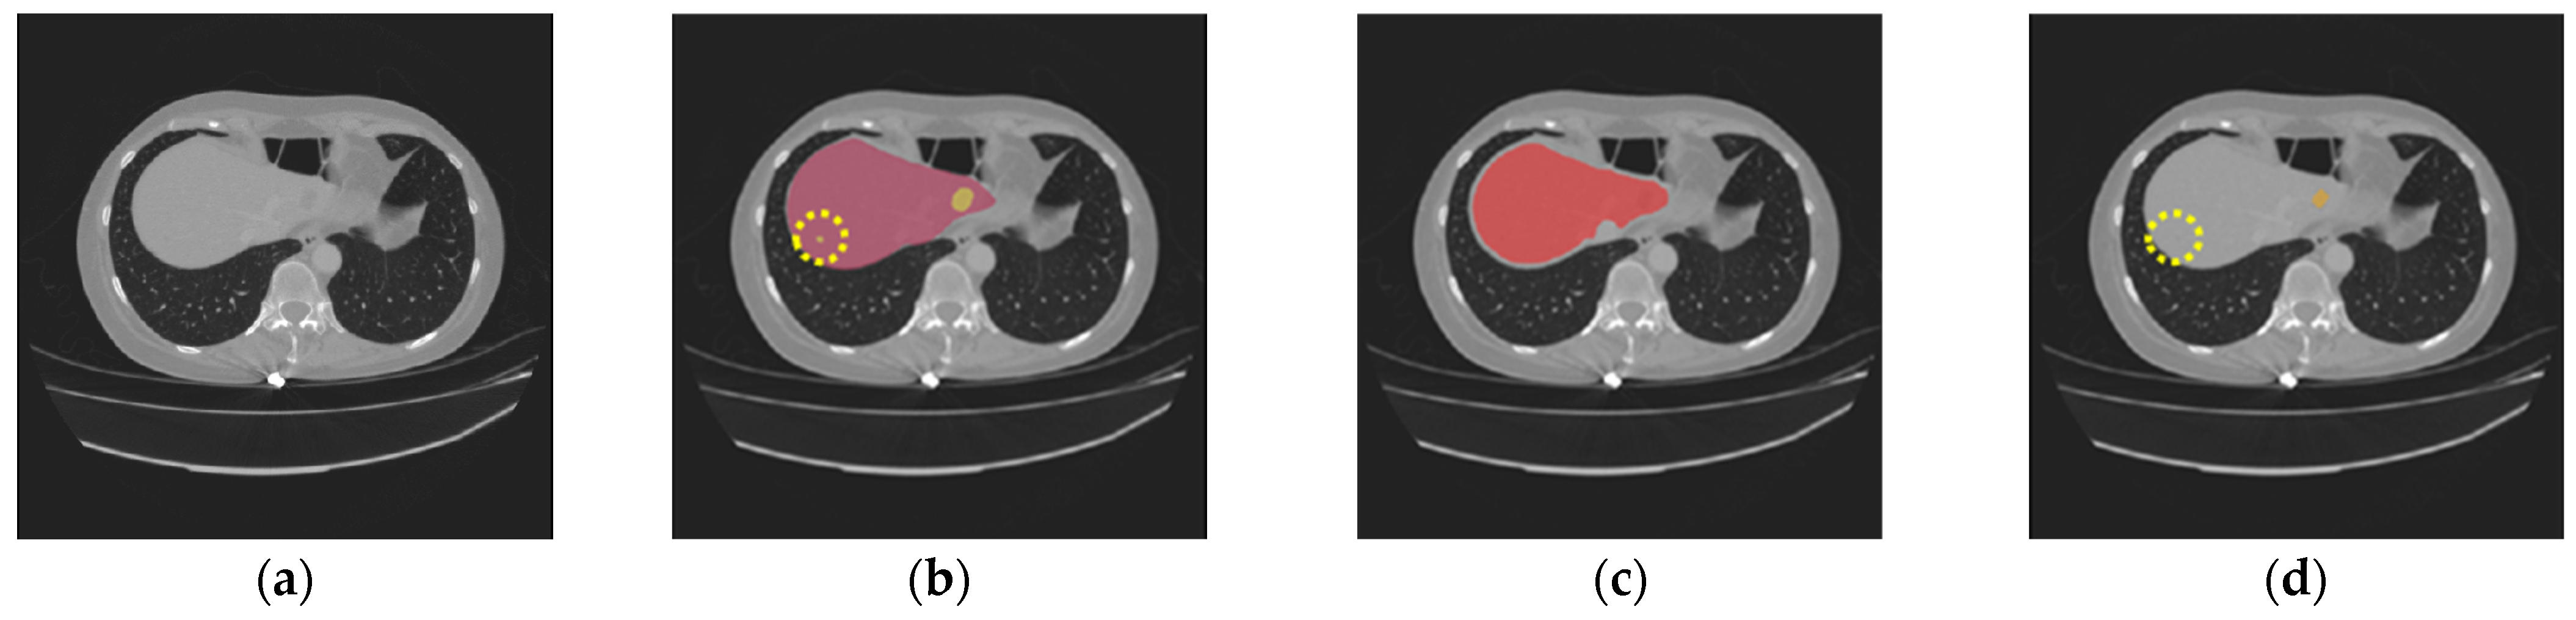

Nevertheless, our study has limitations in certain aspects. The introduction of the two gradient-enhanced encoders increases the complexity level of our model and therefore the computational cost. Furthermore, the tumor segmentation performance can be affected by the liver segmentation performance. The proposed method achieved high performance on both the LiTS dataset and the 3DIRCADb dataset, with an average DSC of 97.38% and 97.50% for liver segmentation, respectively. However, in some cases, tumors may be missing in the segmented liver region, as shown in Figure 9c. Then, in the masking step, those tumors will be excluded from the CT images masked by the extracted liver region, which will be used as the input for tumor segmentation. In that case, those tumors will be missing in tumor segmentation, as shown in Figure 9d. In addition, our model may occasionally miss segmenting some extremely small tumors, as shown in Figure 10. This could be caused by tumor size imbalance and biased annotation for small lesions in the public datasets used for our model development. For our future work, the proposed two-step liver tumor segmentation pipeline can be reduced to a single-step pipeline by applying an end-to-end framework. This would enable a direct extraction of tumors from the original CT scans, thereby reducing computational costs and potentially enhancing the robustness of the segmentation process. Furthermore, the sizes of the datasets used for model training and evaluation are relatively small. To strengthen the experimental validity, the performance of the proposed model needs to be further evaluated using k-fold cross-validation or a larger dataset. Lastly, the ablation study is limited in scope and primarily focuses on the effect of post-processing. Though the ablation study in our previous work [19] concluded that the inclusion of the proposed gradient-enhanced encoders and a hybrid loss function that incorporates the HD loss are effective in improving the performance of liver segmentation, their effects on liver tumor segmentation were not studied in the current study. For future work, a comprehensive ablation study that analyzes the impacts of the gradient-enhanced encoders, the proposed hybrid loss function, and the EPA blocks on improving liver tumor segmentation performance will be conducted.

Figure 9. The following are missing in the final tumor segmentation results due to the missing tumors in liver segmentation results: (a) the original CT slice; (b) the ground truth for the liver (red) and tumors (orange); (c) the liver segmentation result with two tumors missing (highlighted in dotted circles); (d) the tumor segmentation results (orange) with two tumors missing (highlighted in dotted circles).